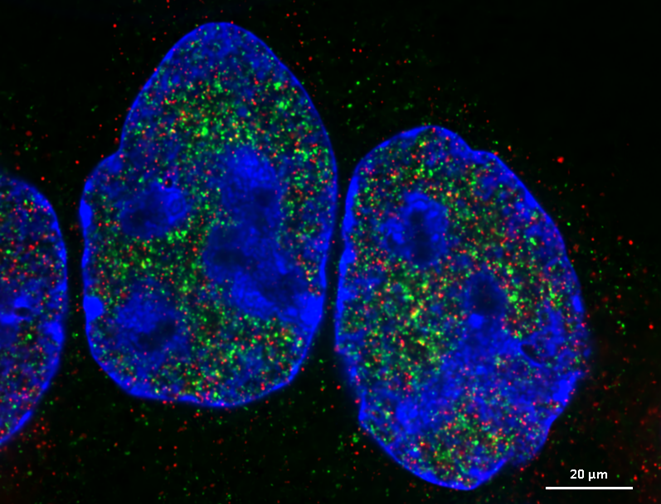

Figure 1. Expansion microscopy of human colorectal carcinoma (HCT) cells. HCT cells were labelled with DAPI and indirect immunofluorescence for Pol2S5P (shown in green) and ZC3H4 (shown in red), expanded of a factor of ~ 6 and acquired with the CrestOptics X-Light V3 Spinning Disk Confocal. A single plane is shown. Scale bar: 20 µm.